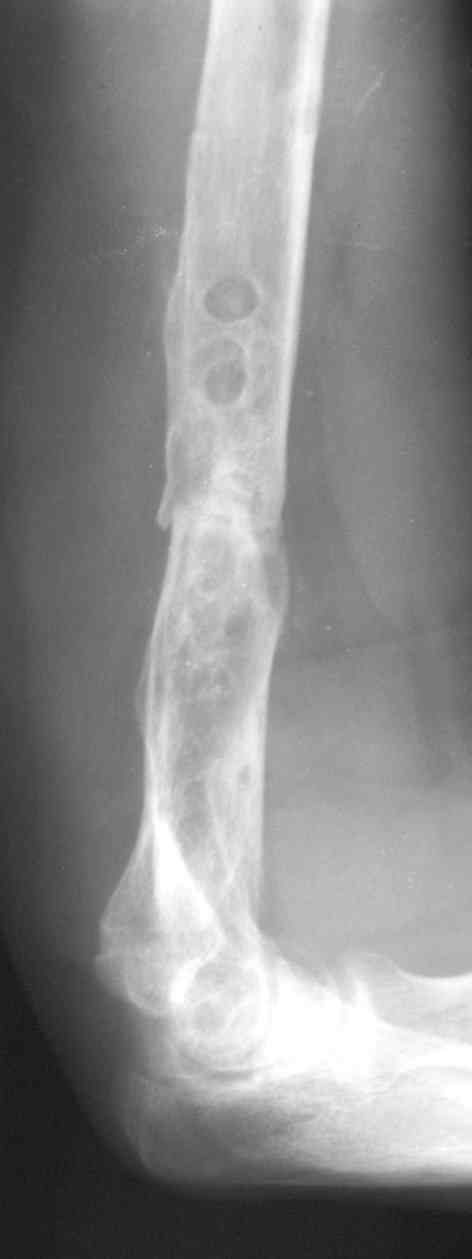

[Ortho] ложный сустав после остеосинтеза плеча

В подобном случае мы бы применили  чрескостный остеосинтез. Пример - в

приложении.